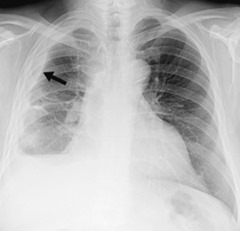

We'll deliver the guide overnight and free of charge. Doctors may also use one or more other imaging tests to make a diagnosis. Feb 27, 2020 · people diagnosed with mesothelioma have aggressive cancer that is caused by asbestos exposure. When a mesothelioma tumor is present on the membrane of the lungs, it may appear as an abnormally white area. Our free guide includes information on legal compensation, treatment options, and more. Lung nodules and hilar masses usually result from direct mesothelioma tumor extension into the lung parenchyma and mediastinal structures, such as lymph nodes, the pericardium, and the heart. It can also arise, less commonly, along the abdominal cavity inner (or peritoneal) lining. The diagnosis can be suggested when we see opacities or masses around the pleura, rib destruction, pleural effusion or fluid around the lung, and big lymph nodes.

More images for mesothelioma on chest x ray » Doctors may also use one or more other imaging tests to make a diagnosis. This cancer is incurable, but patients who are diagnosed early have a much greater life expectancy. What are the types of radiology used to diagnose mesothelioma? We'll deliver the guide overnight and free of charge. When a mesothelioma tumor is present on the membrane of the lungs, it may appear as an abnormally white area. Mesothelioma is a rare type of cancer. Mesothelioma can result in breathing difficulties, chest pain, and fever. We'll deliver the guide overnight and free of charge. The diagnosis can be suggested when we see opacities or masses around the pleura, rib destruction, pleural effusion or fluid around the lung, and big lymph nodes. Our free guide includes information on legal compensation, treatment options, and more. Lung nodules and hilar masses usually result from direct mesothelioma tumor extension into the lung parenchyma and mediastinal structures, such as lymph nodes, the pericardium, and the heart. Feb 27, 2020 · people diagnosed with mesothelioma have aggressive cancer that is caused by asbestos exposure.

These finding will often prompt further testing with a chest ct. Feb 27, 2020 · people diagnosed with mesothelioma have aggressive cancer that is caused by asbestos exposure. The diagnosis can be suggested when we see opacities or masses around the pleura, rib destruction, pleural effusion or fluid around the lung, and big lymph nodes. Mesothelioma is a rare type of cancer. More images for mesothelioma on chest x ray » What does a chest x ray reveal? This ability enables the medical professional to observe whether or not the mesothelioma tumor has metastasized and spread to other areas outside of the pleural cavity. We'll deliver the guide overnight and free of charge.